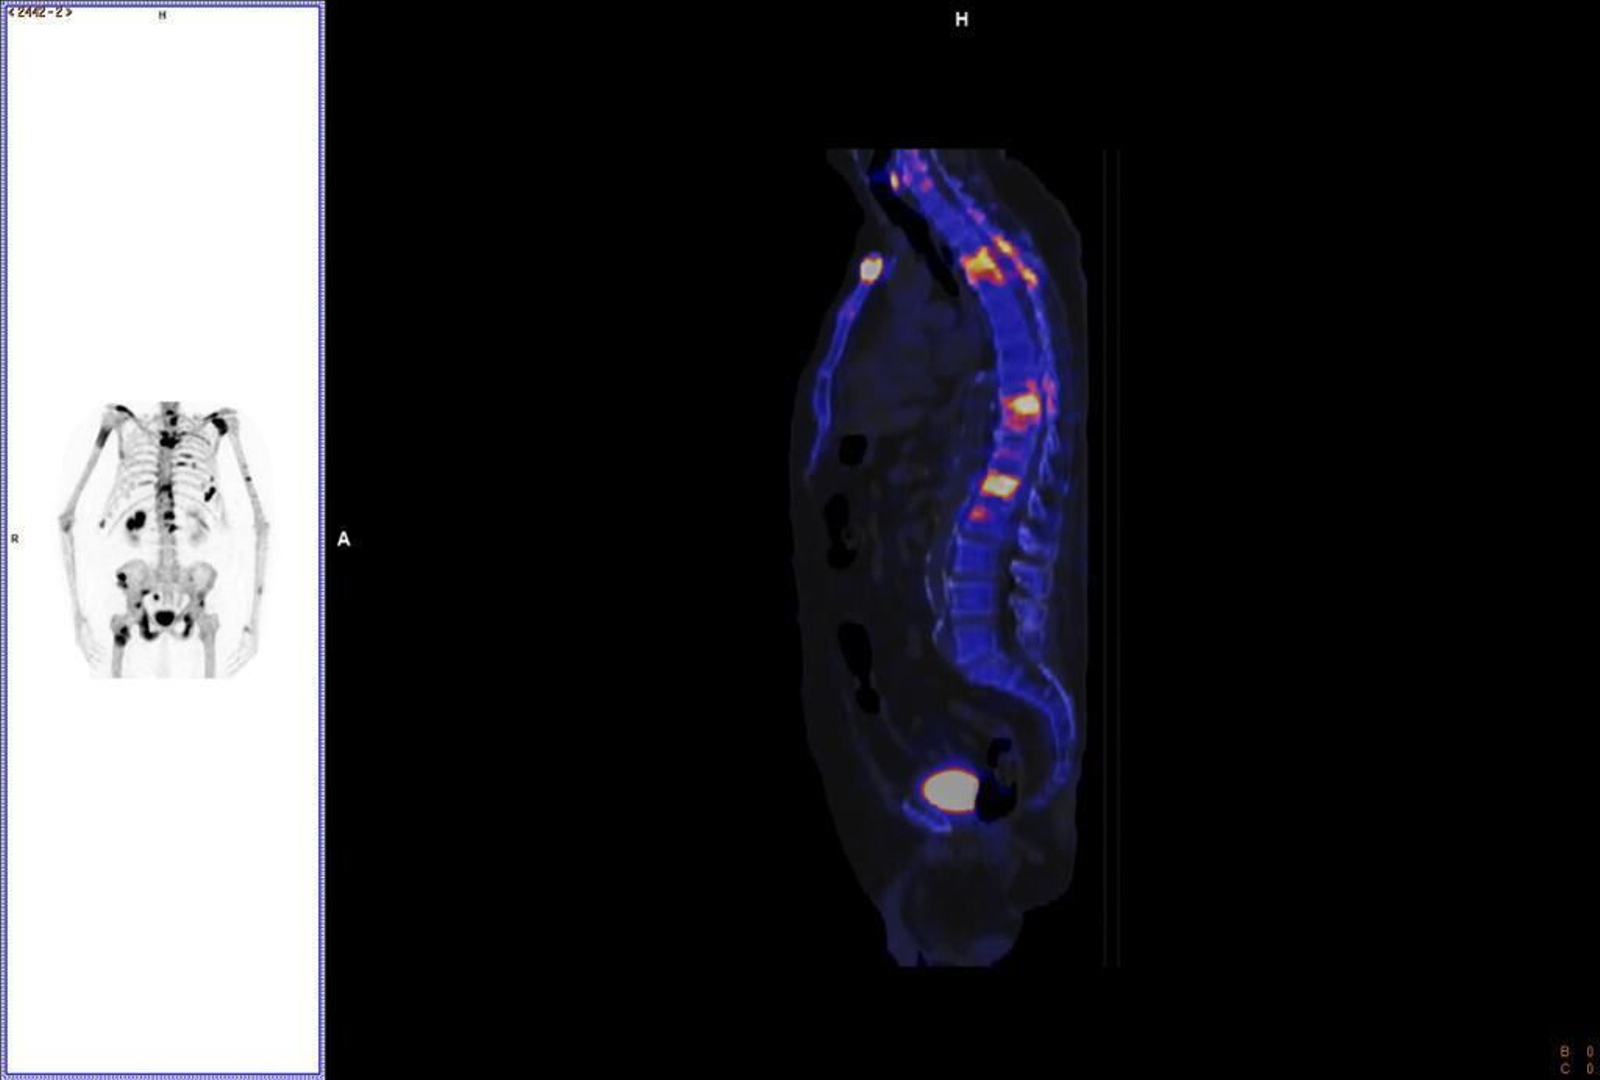

El Hospital Reina Sofía de Córdoba ha puesto en marcha la técnica Xbone, un nuevo procedimiento de reconstrucción de gammagrafía ósea que permite mejorar la resolución y la detección de lesiones metastásicas, y facilita un tratamiento más preciso y precoz.

Un tratamiento que mejora la precisión del diagnóstico, ya que identifica hasta un 20% más de lesiones que el estudio planar y un 10% más que cuando se utiliza la reconstrucción convencional SPECT/TC.

El diagnóstico de este perfil de pacientes (cáncer oligometastásico) se ha incrementado en el último año, algo especialmente relevante en tumores como el cáncer de próstata, dado que un tercio de las personas que lo padecen tendrán metástasis a lo largo de su evolución y el 70% de éstas serán en la columna, con la repercusión que esto implica en su calidad de vida.